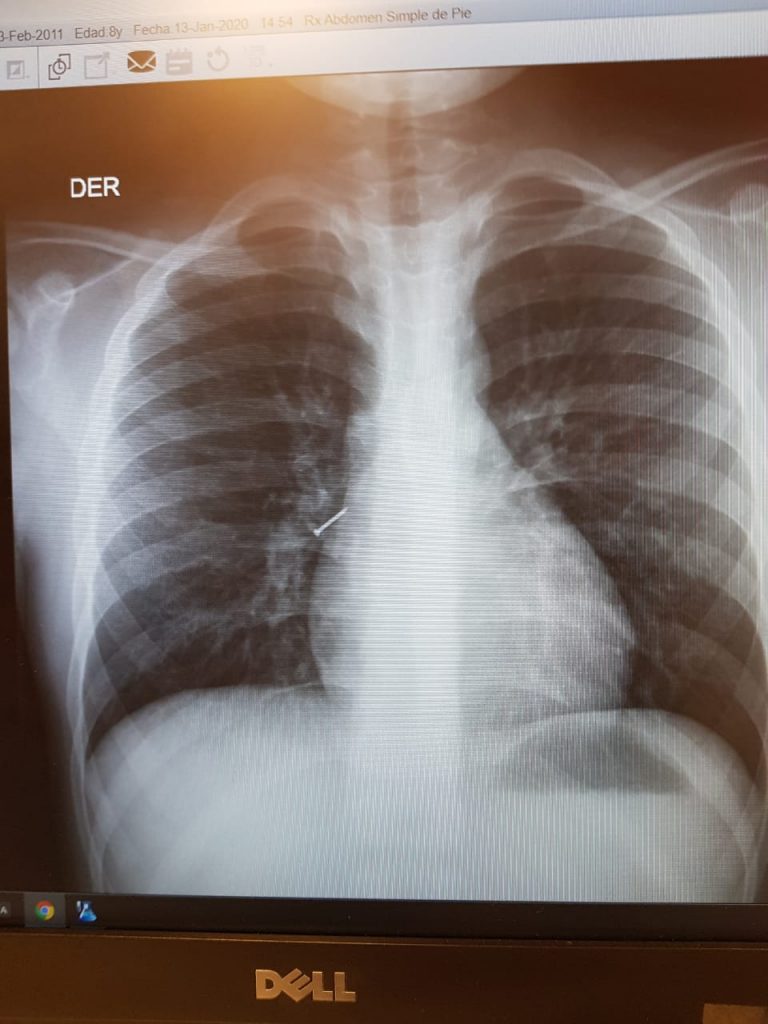

Un menor tuvo que ser operado de urgencia tras tragar un clavo, quedando peligrosamente en su torax. Desde el hospital Carlos Cisternas indican que esta condición es sumamente compleja, el año pasado misma condición costó la vida de dos pacientes puesto que acudieron tarde al recinto.

Es por esto que se destaca esta inédita cirugía la que permitió salvar la vida del menor y a la vez se realiza un llamado a la ciudadanía a acudir de forma inmediata al recinto en caso que de que se ingiera un clavo u otro objeto punzante.